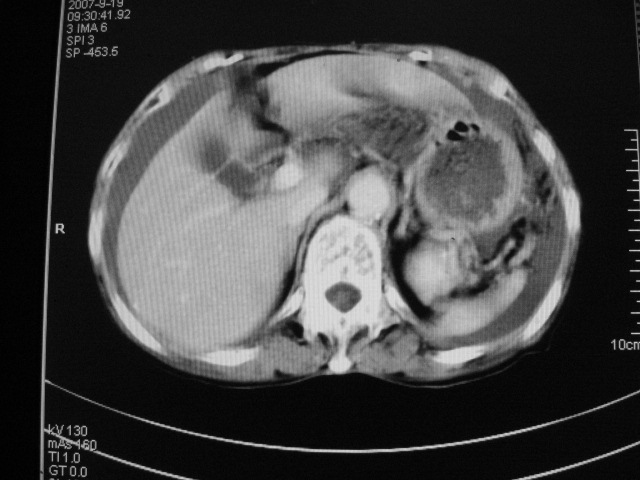

以下是引用默契在2007-9-20 17:29:00的发言:[br][br] [br] 考虑:1、胆囊占位性病变(以癌可能性大);[br] 2、中量腹水。 [br] [br]

以下是引用快乐男生在2007-9-20 15:32:00的发言:[br]图像质量不好:[br]胆囊增大,囊壁增厚,[br]可见结节突出囊腔内,[br]增强后与囊壁相仿.[br]考虑多为胆囊慢性炎症伴有胆囊体部的息肉